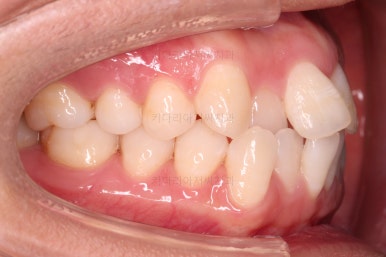

부산교정잘하는치과 초진 시 입안의 모습입ㄴ디ㅏ.

맞물림은 크게 나쁜 편은 아니었고요.

앞니 쪽이 위아래가 다 삐뚤고, 위에 작은 앞니 하나가 거꾸로 물리는 상태였습니다.

거꾸로 물리는 상황에서 특히 아래 앞니는 점점 잇몸이 꺼지는 증상이 생기면서 장기적인 치아의 수명에 영향을 주게 됩니다.